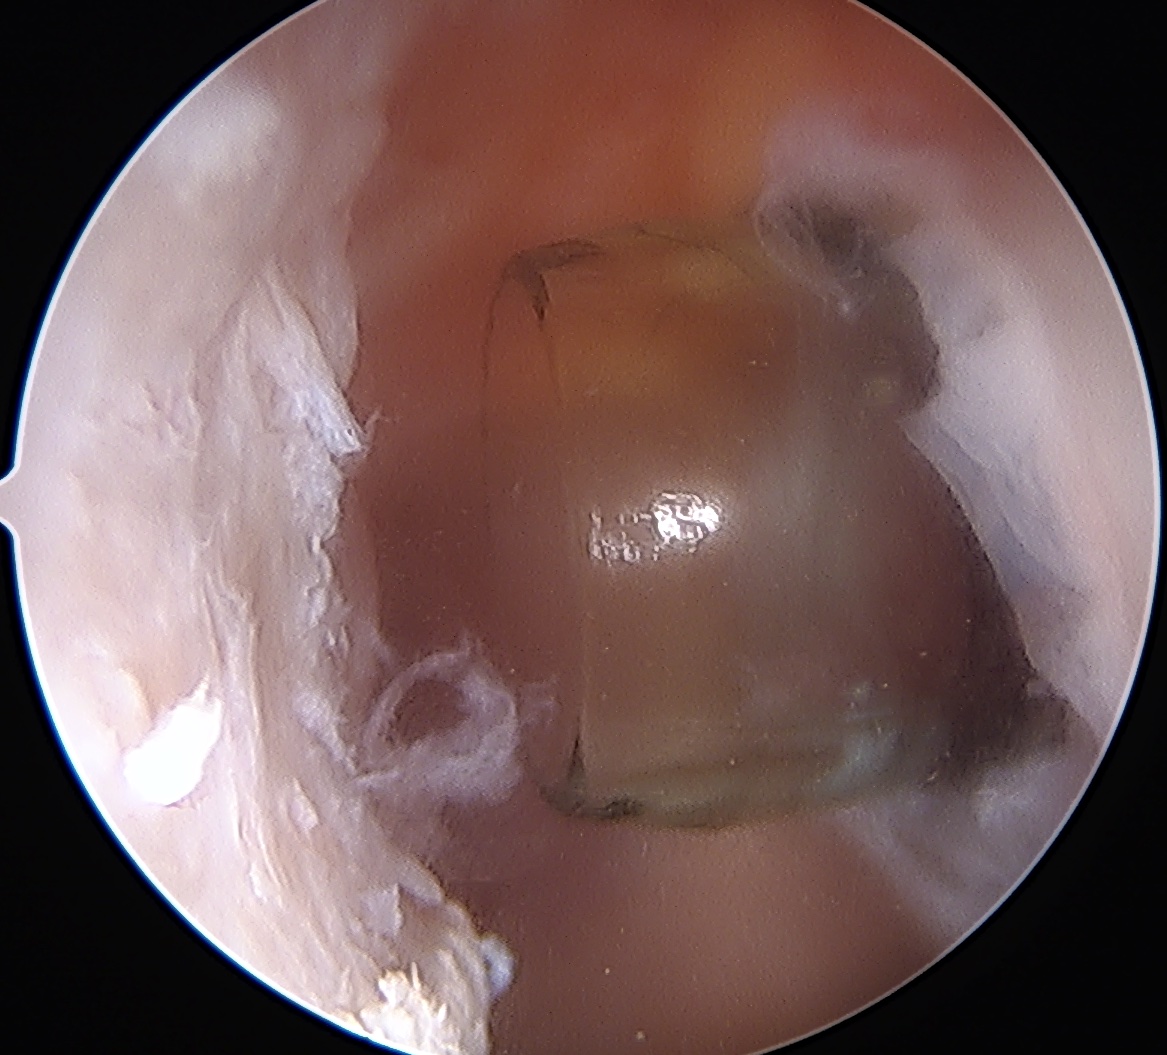

Tying knots under direct vision in the subdeltoid space using double pulley technique

End result